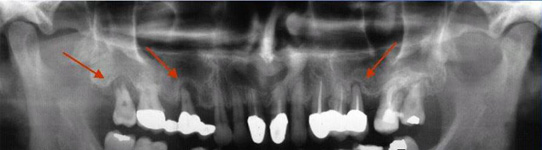

Onemocnění parodontu patří ke druhému nejčastějšímu onemocnění v dutině ústní, ihned po zubním kazu. Nejčastějším problémem je gingivitis- zánět dásní a také parodontitis - zánětlivé onemocnění postihující závěsný aparát zubů, přilehlou dáseň i kost. Mezi časné projevy gingivitidy patří krvácení dásní, které může v případě parodontitidy přejít ve tvorbu parodontálních chobotů, spojené se zápachem z úst, tvorbou hnisu, bolestmi a viklavostí zubů v důsledku ztráty kosti. Tomuto onemocnění se dá úspěšně předcházet pravidelnými kontrolami, sanací chrupu a péčí v rámci dentální hygieny.